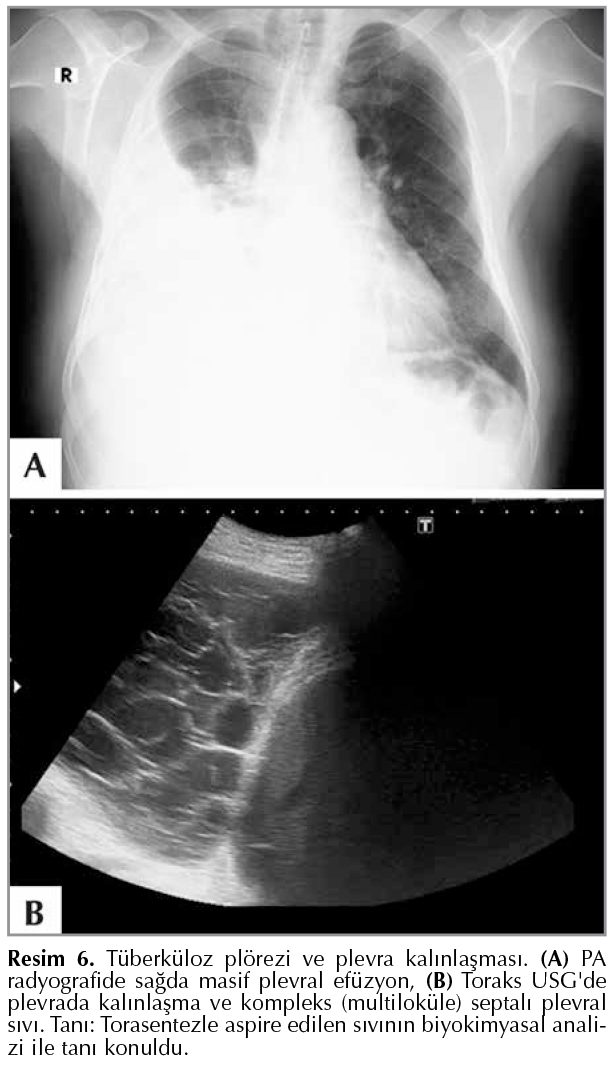

Tuberkuloz Ve Toraks Plevral Hastaliklarin Goruntulenmesi Akciger Grafisi Temelinde Goruntuleme Yontemlerinin Degerlendirilmesi